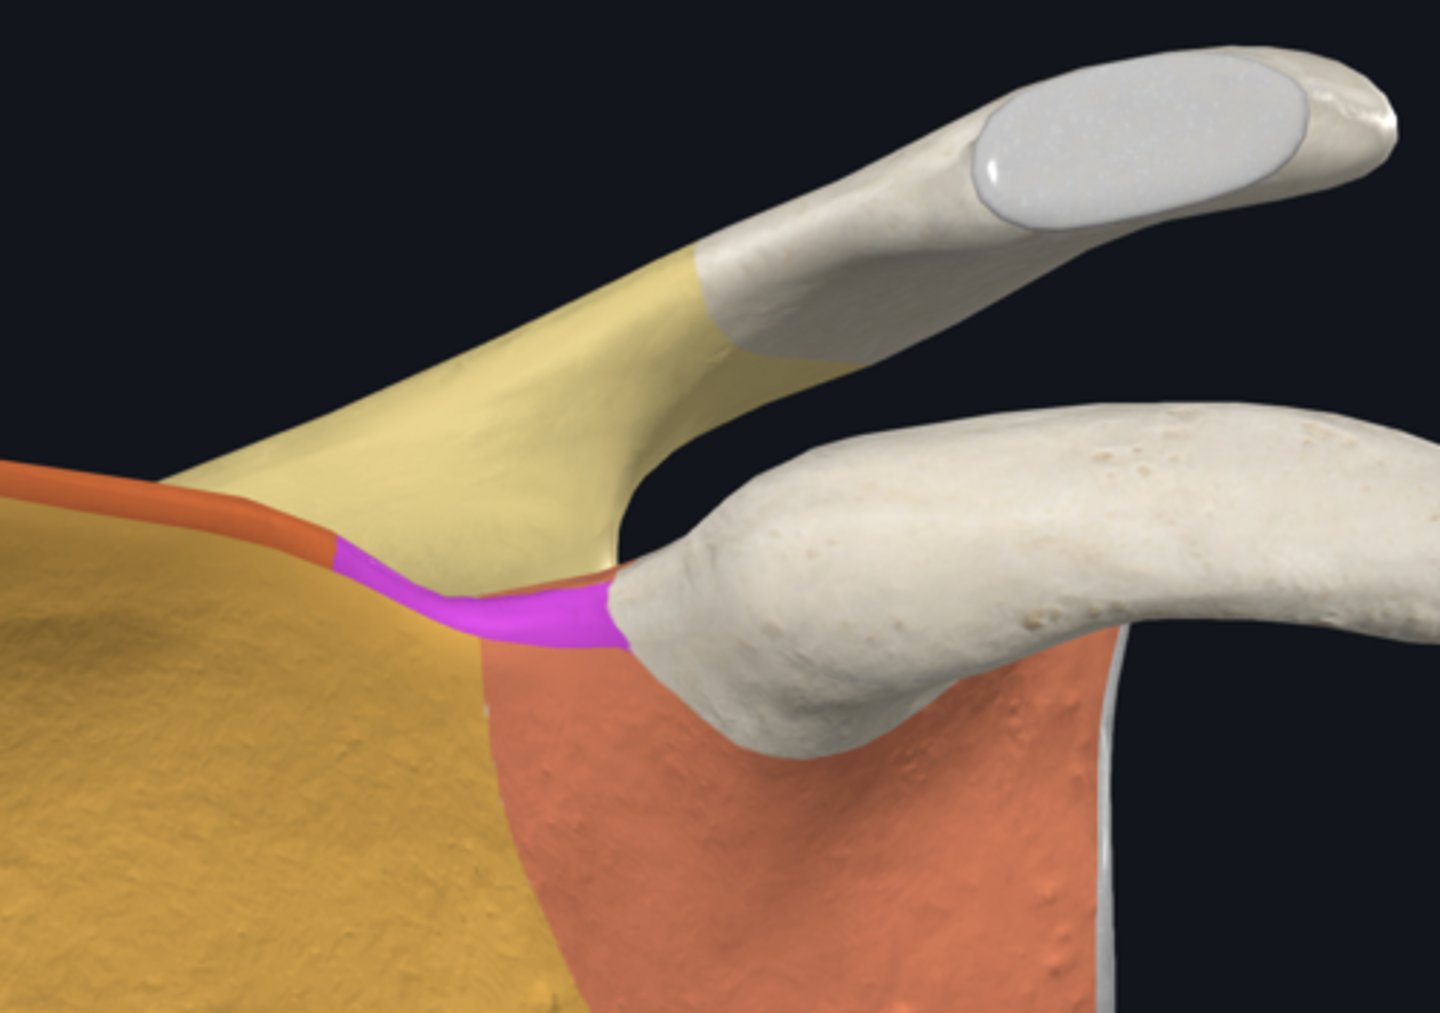

Acromion

Coracoid process

acromial angle

clavicular facet

glenoid fossa

infraglenoid tubercle

spine of scapula

supraglenoid notch

supraglenoid tubercle